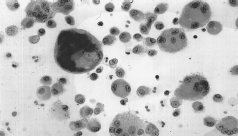

As mudanças nos tamanhos das partículas podem alterar a via e a intensidade de absorção. No caso de nanopartículas (nm), suas propriedades podem ser muito diferentes do mesmo material em tamanhos grandes. Por exemplo, o dióxido de titânio (TiO 2 , CAS 13463-67-7), quando em forma de nanopartículas, tem efeitos inflamatórios pulmonares que não podem ser observados quando a exposição se dá na partícula do material com diâmetro ordinário (Buschinelli;Kato, 2011) As partículas insolúveis podem ficar retidas e posteriormente expectoradas (junto com o muco) ou mesmo exaladas (com o ar expirado) ou ainda deglutidas, somando-se à possível penetração por via digestiva. Partículas com diâmetro aerodinâmico (DA) inferior a 10 micra (?m), como no caso dos pósmetálicos de metal-duro, oferecem probabilidade significativa de atingir os alvéolos pulmonares, sendo que esta probabilidade ainda aumenta com a diminuição do DA. Ao atingir os alvéolos dependendo da solubilidade na mucosa diferentes efeitos podem ser observados conforme apresentados nas Fig. 4(a) e 4(b), (Colacioppo, 2020). As partículas insolúveis quando depositadas na região final dos brônquios e alvéolos sendo que o máximo de deposição a ser alcançado por partículas em torno de 1 a 2 micra (µm), que podem ser eliminadas com a reação do tecido pulmonar, através dos macrófagos, que consistem em células sanguíneas especiais (de cerca de 100 a 200 ?m) que quando liberadas, podem englobar, destruir a partícula ou simplesmente mantê-la inerte (fagocitose). A situação se complica com o aumento da quantidade de partículas ou ainda quando a partícula não fica inerte, no caso dos carbonetos, classificados como insolúveis, podem despertar outros mecanismos de defesa imunológica do organismo, mas, estes mecanismos por vezes acabam por desencadear uma pneumoconiose, doença esta que modifica a estrutura do tecido pulmonar e por consequente perda da capacidade de respiração pulmonar sendo que as mais conhecidas são a silicose provocada pela sílica (SiO 2 ) e a asbestose provocada pelo asbesto ou amianto (Colacioppo, 2020).

Moreira et al. (2010), acompanharam um paciente de 27 anos, que trabalhava há 8 anos como afiador de ferramentas de metal-duro (serra, serrotes e facas de corte), trabalhava por oito horas diárias, equivalente a 40 horas semanais, sem o uso do EPI, ou EPR -equipamento de proteção respiratória. Esse profissional utilizava no processo de retificação/afiação um rebolo diamantado sintético, em um ambiente fechado. Baseado na história desse trabalhador, nos exames de imagem (radiografia de tórax) e no exame anatomopatológico, foi feito o diagnóstico de pneumoconiose por metal-duro ou fibrose pulmonar. O tratamento da pneumopatia por exposição a metal-duro envolve o afastamento completo da exposição ao agente nocivo e corticoterapia em doses altas. Quando já existe fibrose pulmonar extensa, uma apresentação de estudo de caso raro, não há significativa resposta ao tratamento.